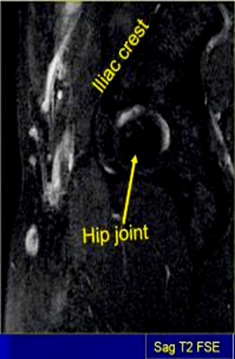

SAG T2 SPAIR TSE 3-4 mm 0.5-1mm SPAIR 20cm Ischial tuberosity to ischial tuberosity (NOT skin to skin)

MRI Pelvis Sports Hernia WO MSK Protocol image 1